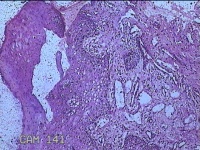

下唇肿物

性别

女

年龄

9岁

临床诊断

唇粘液囊肿

一般病史

下唇肿物1月

标本名称

大体所见

灰白暗红色肿物0.8x0.5x0.2cm一个,表面糜烂。